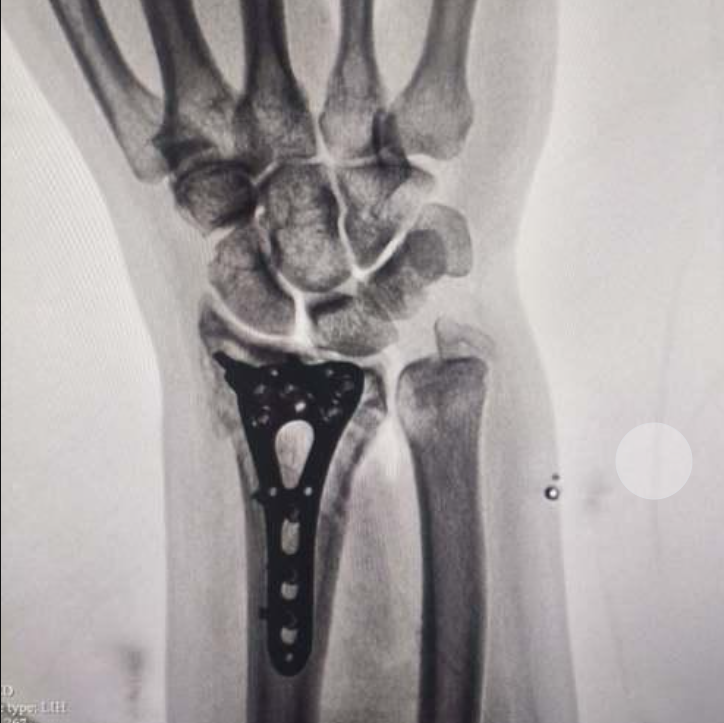

鎖定接骨(gu)板:復(fu)雜骨(gu)折的優選(xuan)方(fang)案

對(dui)于AO分(fen)型中的B、C型骨折(zhe)及粉碎性損傷,橈骨(gu)遠端鎖定接(jie)骨(gu)板(ban)憑借以下優(you)勢(shi)成(cheng)為(wei)臨床首(shou)選(xuan):

1. 解剖型設(she)計:貼合(he)橈骨(gu)遠端形態,減少軟(ruan)組織刺激,降低術后并發癥風險

2. 鎖定螺釘技術:提供角穩(wen)定性,尤其適用于骨質疏松患者,防止(zhi)螺(luo)釘松動

3. 多平面固定(ding):支持多角(jiao)度置釘,有效(xiao)固(gu)定粉碎骨(gu)塊(kuai),恢復關(guan)節面平整(zheng)

4. 早(zao)期康復:術后可早期進行腕(wan)關(guan)節功能(neng)鍛煉(lian),縮短恢(hui)復周(zhou)期

橈骨(gu)遠端鎖定接(jie)骨(gu)板

臨(lin)床價值: 為復(fu)雜關(guan)節(jie)內(nei)骨折提(ti)供穩定固定,降低二次手術風險。結合早期康復(fu)方案,顯著改善患者(zhe)腕關(guan)節(jie)功能評(ping)分(fen)(如Mayo評(ping)分(fen))。

術后(hou)病例(li)圖片

橈骨(gu)(gu)遠端骨(gu)(gu)折手術(shu)解決(jue)方案